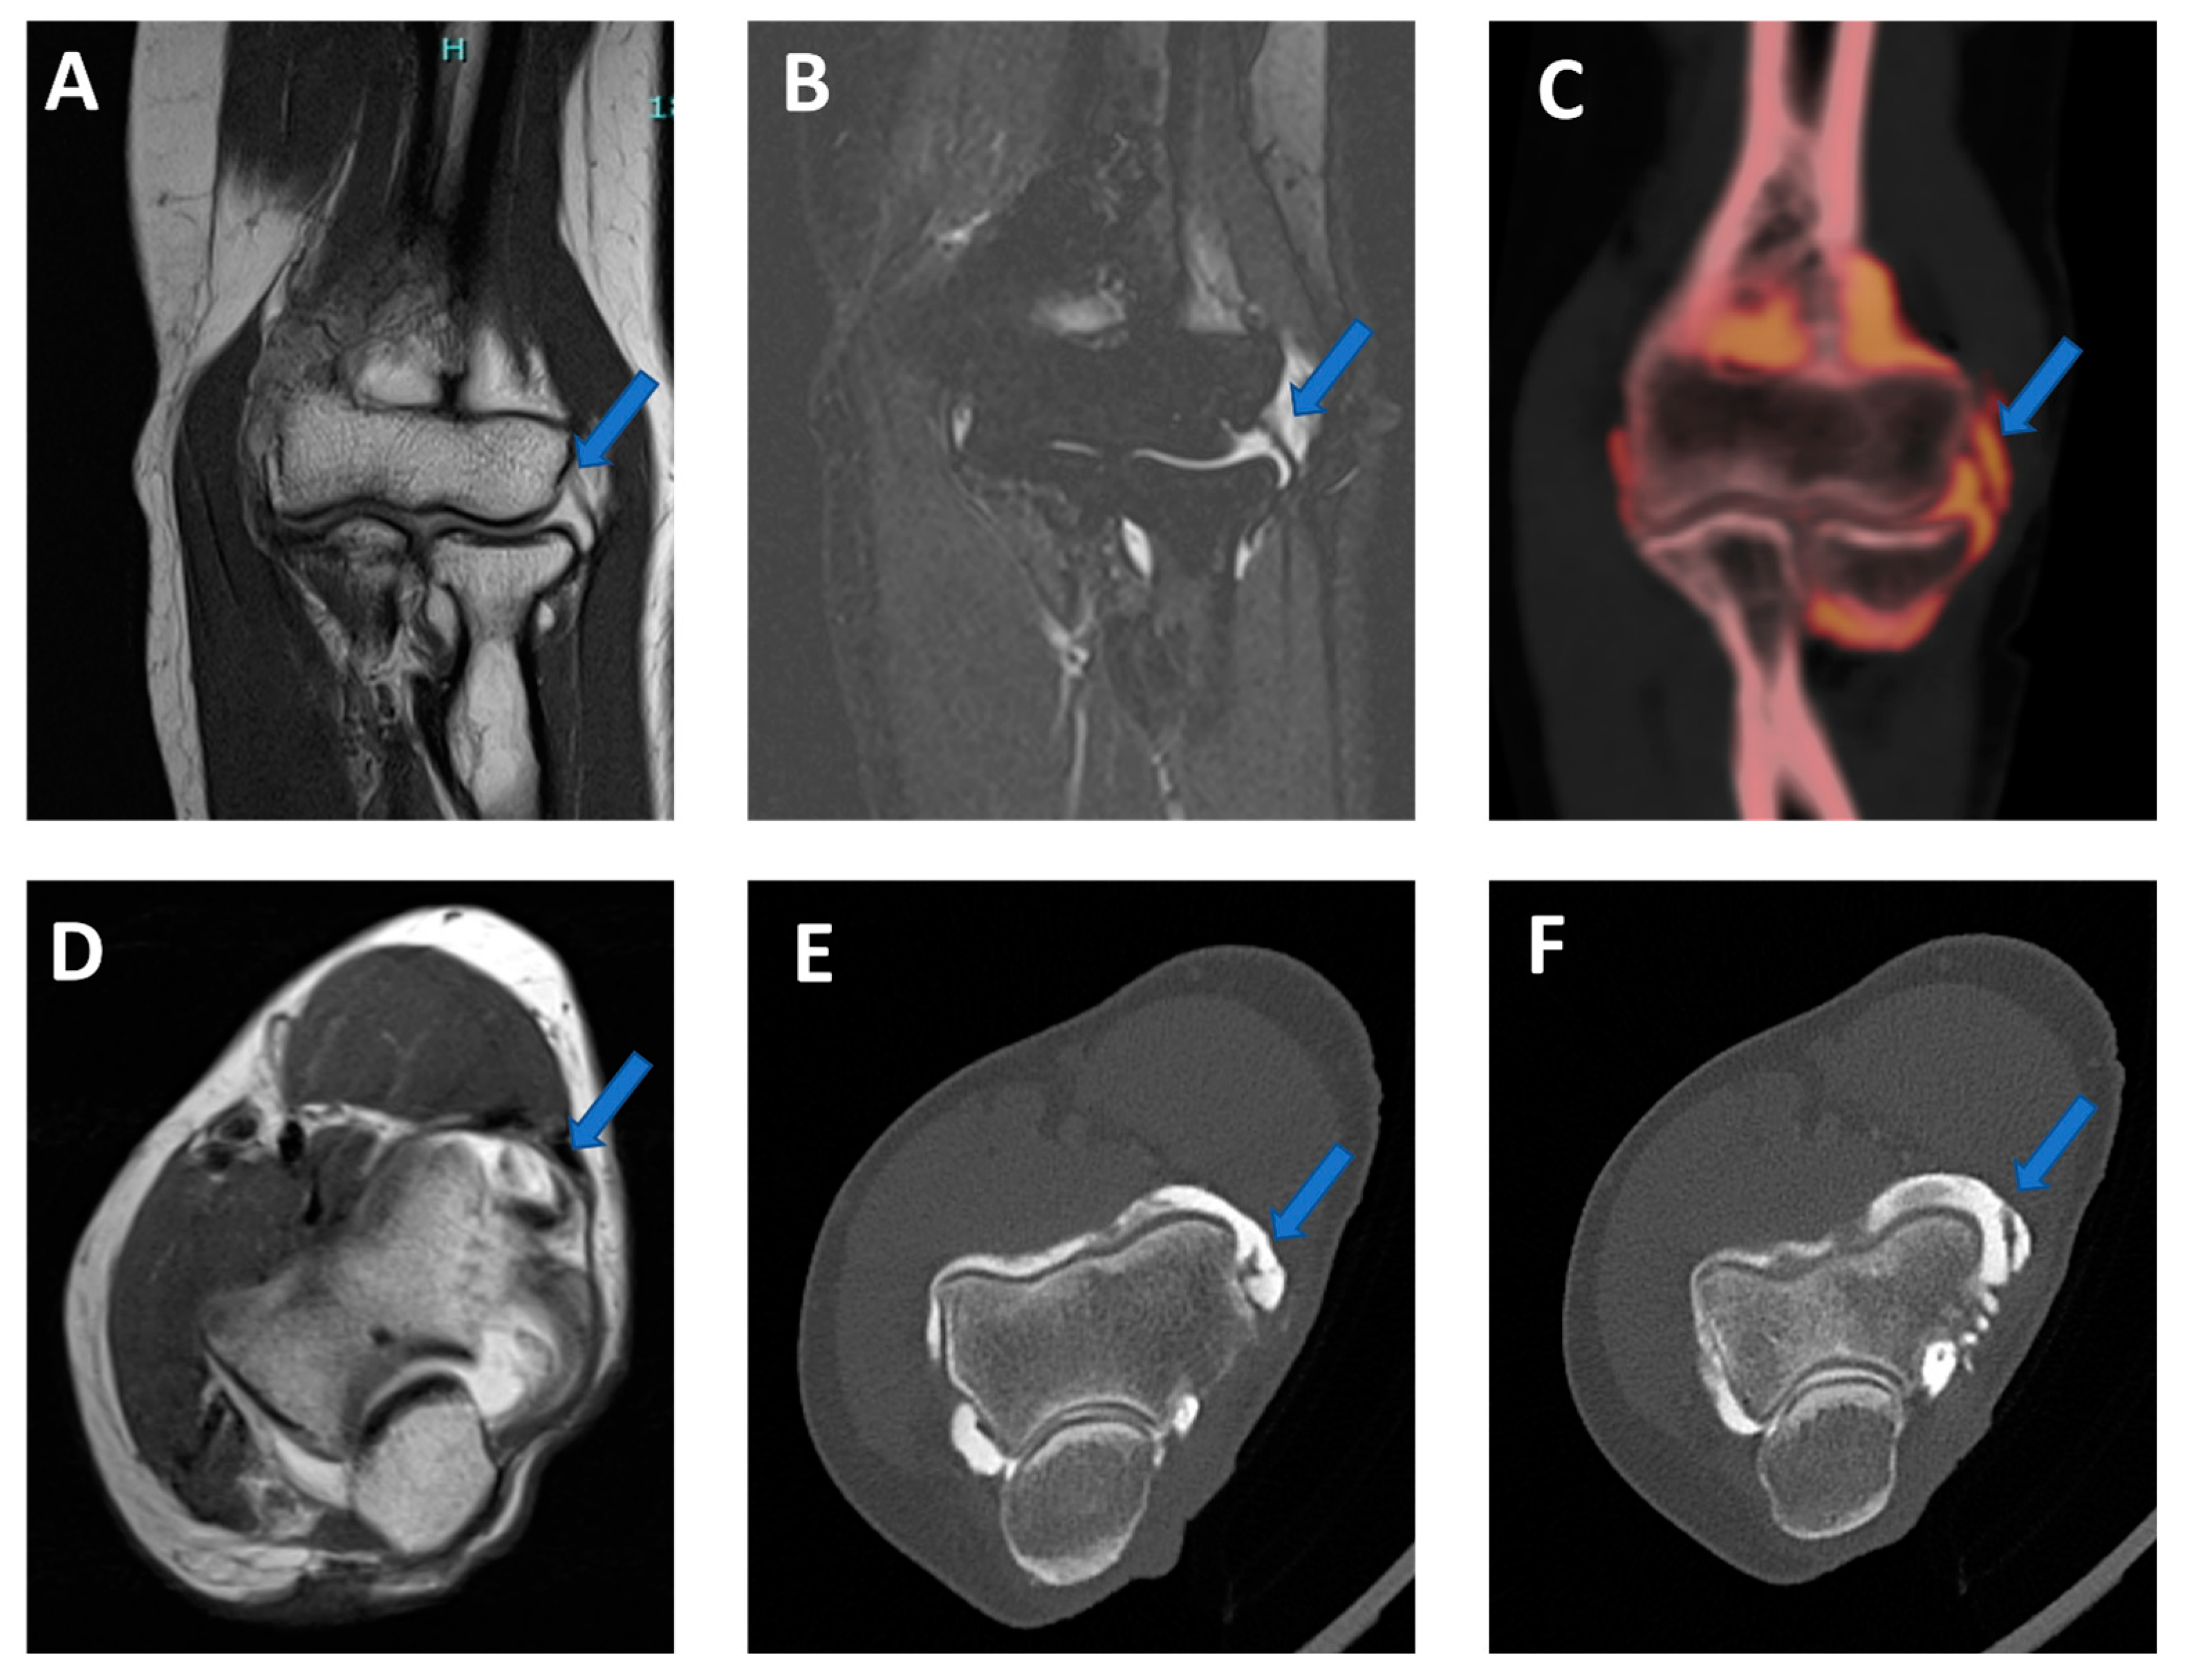

Figure 9. Lateral plica syndrome at elbow arthrography. On the 3 mm coronal STIR and T1 weighted images (A,B), a tiny lateral plica (arrow) is depicted. The same plica is nicely depicted (arrow) on the corresponding reconstructed coronal 0.5 mm DECT iodine map image (C). On the 3 mm axial T1 weighted image (D), a partial volume effect does not allow for the correct image of the plica (arrow) and articular cartilages. On the corresponding 0.5 mm axial DECTA (E,F), the plica (arrow) and the adjacent articular cartilages are beautifully visualized without any artifact.